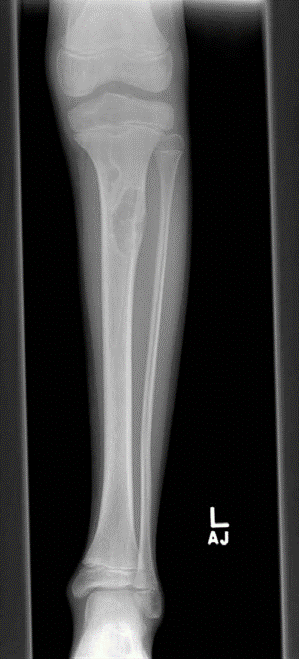

Orthopaedic oncology Structured oral examination question 3: Non-ossifying fibroma EXAMINER : Tell me about t…